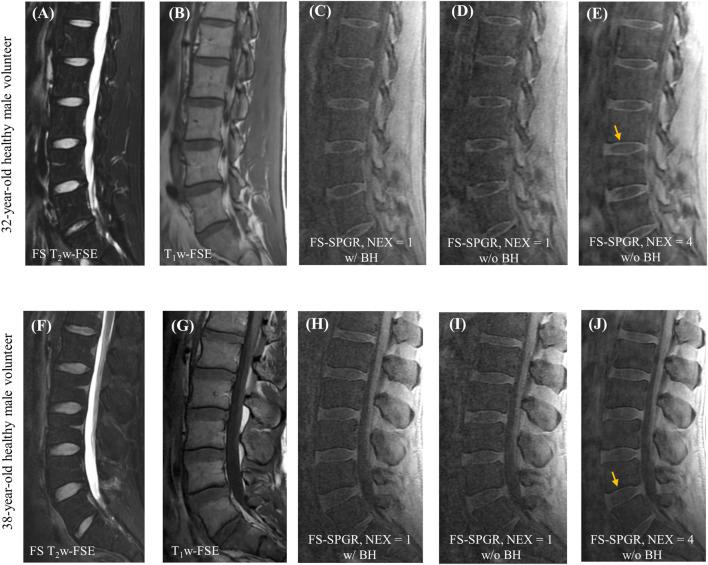

Many spine disorders are caused by disc degeneration or endplate defects. Because nutrients entering the avascular disc are channeled through the cartilaginous endplate (CEP), structural and compositional changes in the CEP may block this solute channel, thereby hindering disc cell function. Therefore, imaging the CEP region is important to improve the diagnostic accuracy of spine disorders. A clinically available T1-weighted and fat-suppressed spoiled gradient recalled-echo (FS-SPGR) sequence was optimized for high-contrast CEP imaging, which utilizes the short T1 property of the CEP. The FS-SPGR scans with and without breath-hold were performed for comparison on healthy subjects. Then, the FS-SPGR sequence which produced optimal image quality was employed for patient scans. In this study, seven asymptomatic volunteers and eight patients with lower back pain were recruited and scanned on a 3T whole-body MRI scanner. Clinical T2-weighted fast spin-echo (T2w-FSE) and T1-weighted FSE (T1w-FSE) sequences were also scanned for comparison. For the asymptomatic volunteers, the FS-SPGR scans under free breathing conditions with NEX = 4 showed much higher contrast-to-noise ratio values between the CEP and bone marrow fat (BMF) (CNR) (i.e., 7.8 ± 1.6) and between the CEP and nucleus pulposus (NP) (CNR) (i.e., 6.1 ± 1.2) compared to free breathing with NEX = 1 (CNR: 4.0 ± 1.1 and CNR: 2.5 ± 0.9) and breath-hold condition with NEX = 1 (CNR: 4.2 ± 1.3 and CNR: 2.8 ± 1.3). The CEP regions showed bright linear signals with high contrast in the T1-weighted FS-SPGR images in the controls, while irregularities of the CEP were found in the patients. We have developed a T1-weighted 3D FS-SPGR sequence to image the CEP that is readily translatable to clinical settings. The proposed sequence can be used to highlight the CEP region and shows promise for the detection of intervertebral disc abnormalities.